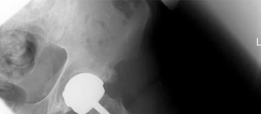

توضح الصور الإشعاعية أعلاه حالة الفصال العظمي في مفصل الورك الأيسر للمريض.

تُظهر هذه الصور الإشعاعية تآكل الغضاريف وتغيرات في بنية العظام، مما يؤكد تشخيص الفصال العظمي.